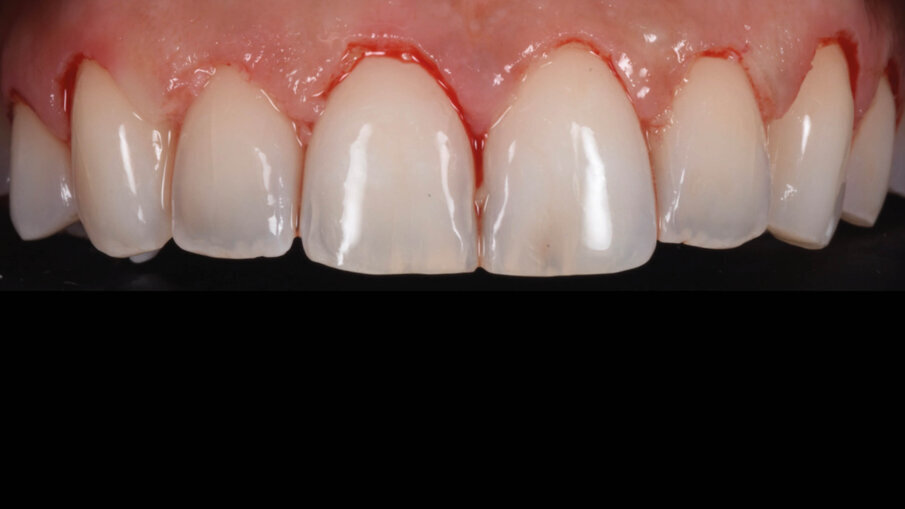

La suture, in questo caso 5.0 riassorbibili (Flysorb mono, Butterfly, Cavenago Brianza, MI) hanno il solo scopo di mantenere i tessuti molli nella posizione corretta per agevolarne il riattacco e la guarigione, i nodi quando possibili vengono applicati sul versante palatale (Fig. 15). A novanta giorni dalla chirurgia si può apprezzare l’ottima guarigione e maturazione dei tessuti e come l’interfaccia dente gengiva sia migliorata sia all’esame intra che extra-orale (Fig. 16). Le foto intra ed extra-orali fatte a 24 mesi dall’intervento testimoniano l’ottimo risultato ottenuto e la sua stabilità (Fig. 17).

Fig. 16_Follow up a 90 giorni.